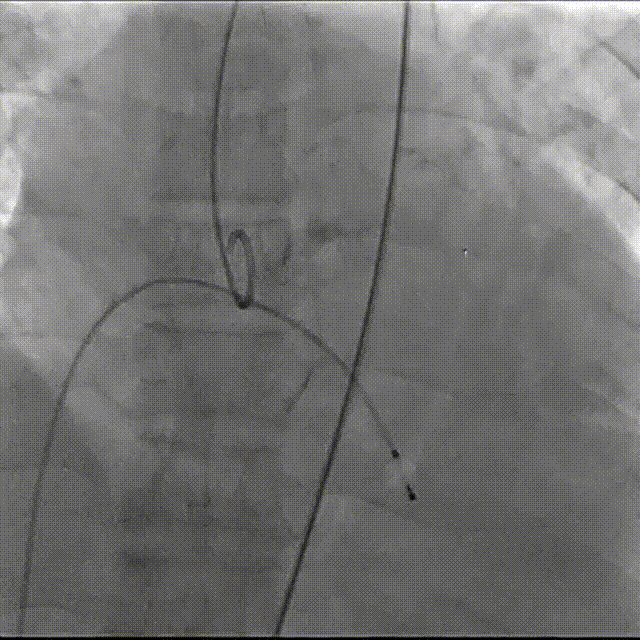

第一次瓣膜定位,心脏再次停跳,按压复律

第二次完全释放

球囊后扩